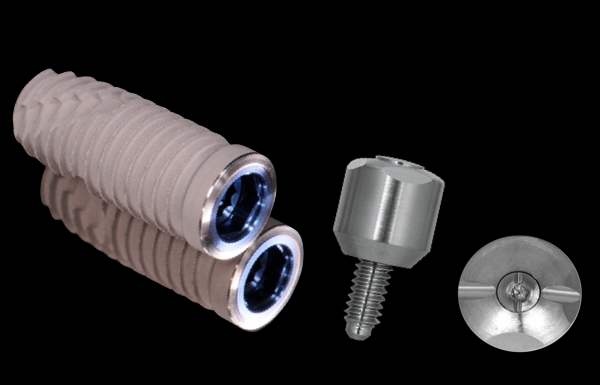

High strength Zirconia ceramics are the best option for full arch implant restorations. Resin and denture teeth alternatives have a 90% complication and failure rate.

High strength Zirconia ceramics are the best option for full arch implant restorations. Resin and denture teeth alternatives have a 90% complication and failure rate.